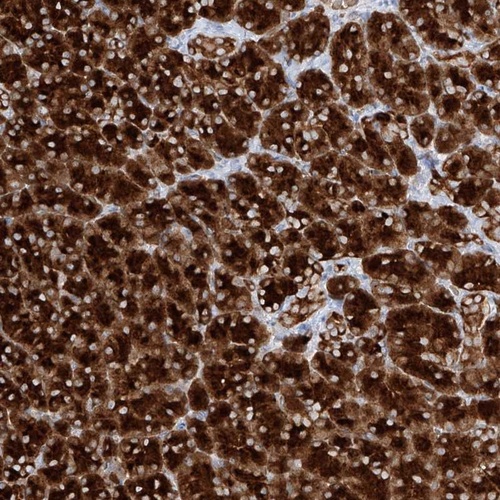

Immunohistochemical staining of human pancreas shows strong cytoplasmic positivity in exocrine glandular cells.